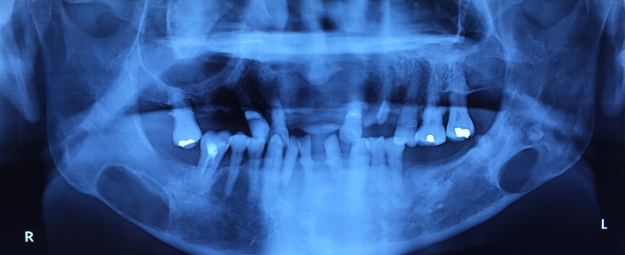

16

Q

What is happening in this image and tx?

A

Osteomyelitis

• Inferior border of right mandible- expansion.

• Pathological

• Well defined

• Calcification within it surrounded by radiolucency

• Dead primary teeth with chronic infection that has spread to bone marrow

• Tx: excision of bone sequestrum

17

What is this?